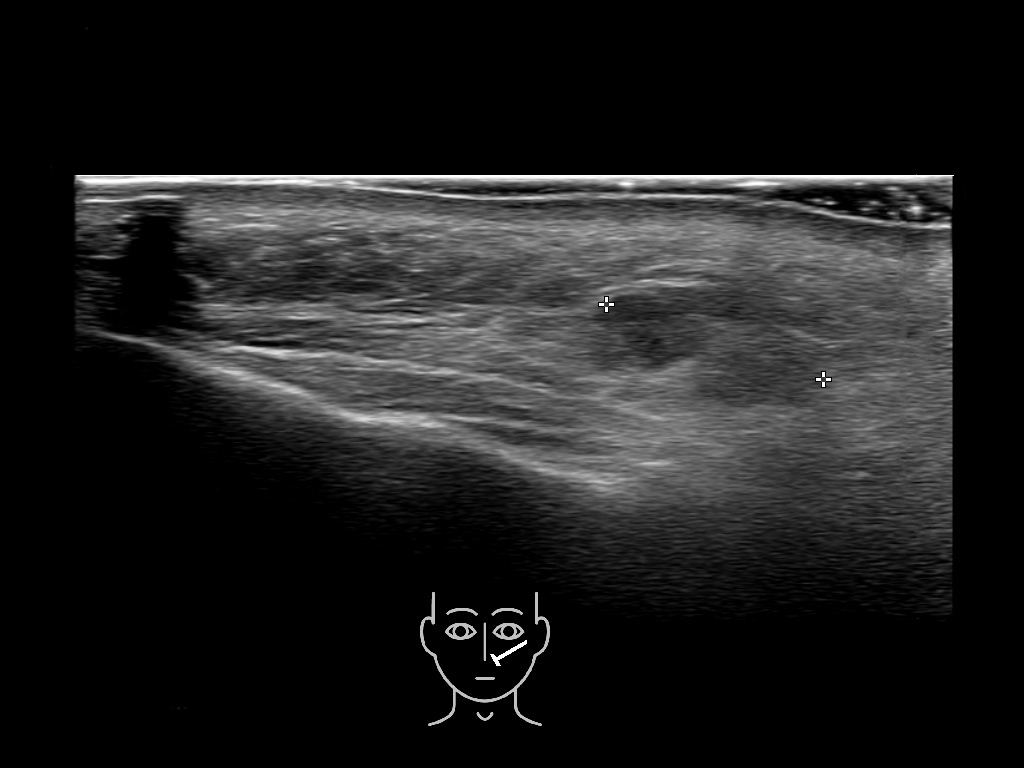

With ultrasound signs of inflammation can be visualized. Edema can be seen as a hyperechoic appearance of the subcutaneous fat, sometimes separated by hypoechoic fluid filled area’s, known as cobblestone appearance. Increased vascularization (hypervascularity) can be seen on colour Doppler. An abscess will appear as a fluid collection appearing as an irregular hypoechoic area with heterogeneous internal echoes and a thickened wall. Posterior acoustic enhancement can be present, and there is vascularity around but not within the mass. Under ultrasound guidance, abscesses can be managed by needle aspirations (18G) under antibiotic cover.

Study the first image to recognize the different layers. If you are sure about the layers, swipe to the second image to view the answer (if applicable).